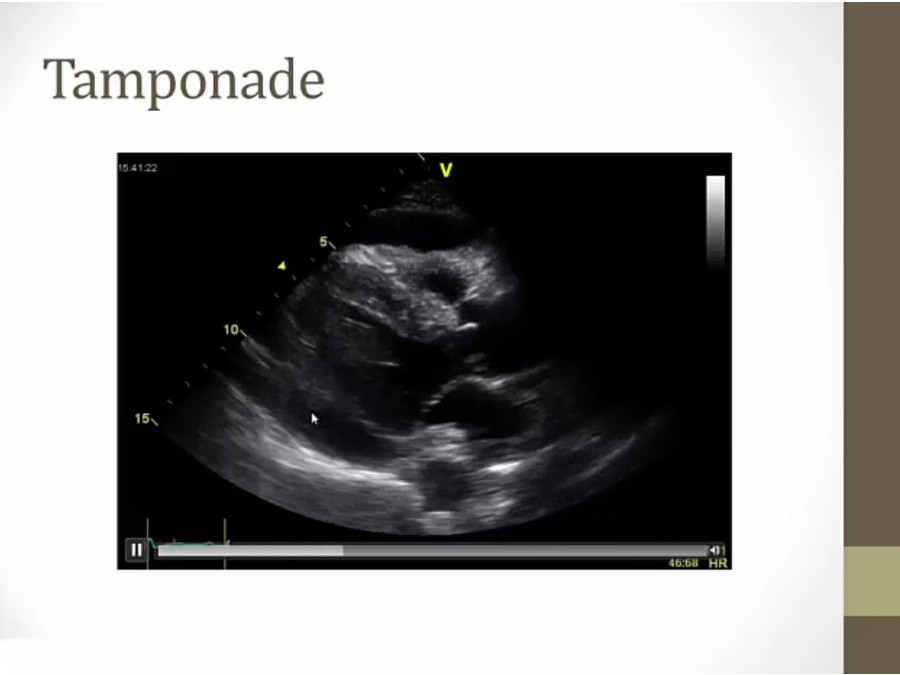

Tamponade

cancer pts developing dyspnea: tamponade

wall of fluid muffle heart sounds

black band around infralateral wall (lower left) and in front (top)

tamponade: RV cannot increase in size, all its increase in size bulges into LV

EKG: rare, tall and short QRS, heart swinging inside fluid

tamponade: RV contraction, makes room in pericardium for fluid to move away from RA to RV, allow RA to relax more, steep x descent

late diastolic collapse of RA